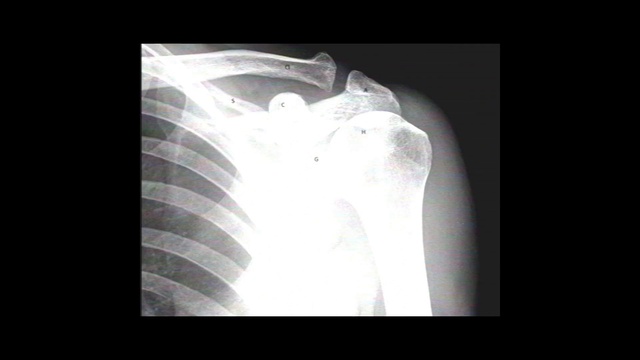

Best Video References: Fracture

Featured videos selected by a smart neural network algorithm